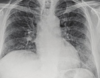

12

Q

A

Consolidación alveolar